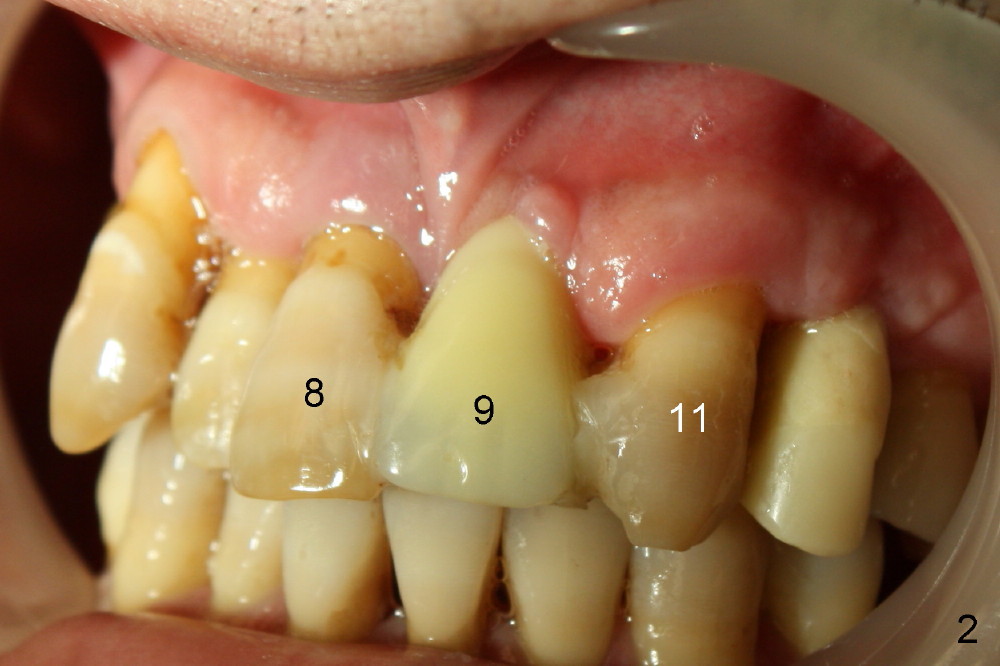

A 41-year-old man has poor dentition (Fig.1: #12 immediate provisional). It appears that #10 is congenitally missing. A temporary bridge is fabricated (Fig.1: #8-11) when #9 is reportedly extracted. Recently bonding between #9 pontic and #11 detaches. The bridge is loose (Fig.2). The tooth #8 is periodontally compromised (Fig.3,5: CT sagittal and coronal sections, respectively).